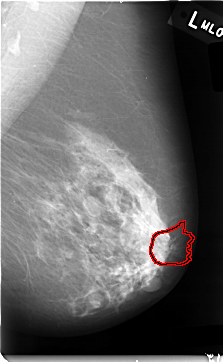

C_0006_1.RIGHT_MLO

FILE: C_0006_1.RIGHT_MLO.OVERLAY

TOTAL_ABNORMALITIES 1

ABNORMALITY 1

LESION_TYPE MASS SHAPE IRREGULAR MARGINS SPICULATED

ASSESSMENT 5

SUBTLETY 5

PATHOLOGY MALIGNANT

TOTAL_OUTLINES 1

BOUNDARY